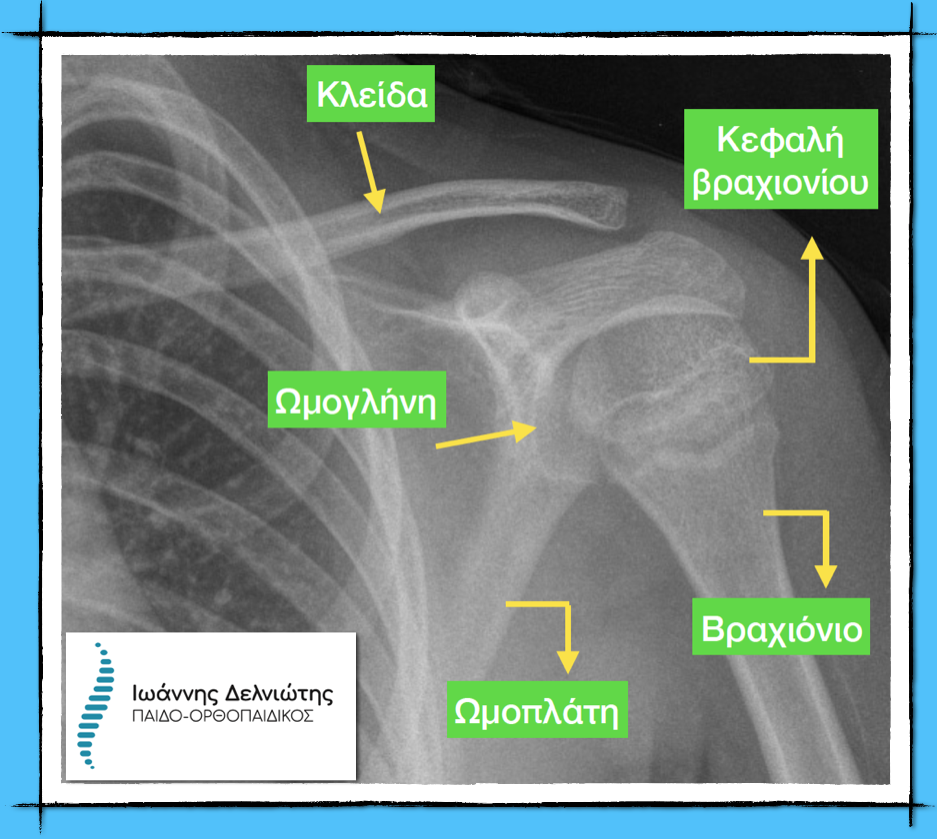

Η κλείδα είναι ένα οστό, το οποίο κοιτώντας τον ανθρώπινο οργανισμό από μπροστά φαίνεται να είναι σε ευθεία, αλλά αν κανείς κοιτάξει το ανθρώπινο σώμα από πάνω θα καταλάβει ότι η κλείδα είναι ένα οστό σε σχήμα S.

Αποτελεί (μαζί και με την ωμοπλάτη) την κύρια σύνδεση μεταξύ του άνω άκρου και του κυρίως κορμού. Για να δείτε μια φυσιολογική σχέση της κλείδας με τα γειτονικά ανατομικά στοιχεία δείτε την εικόνα παρακάτω.